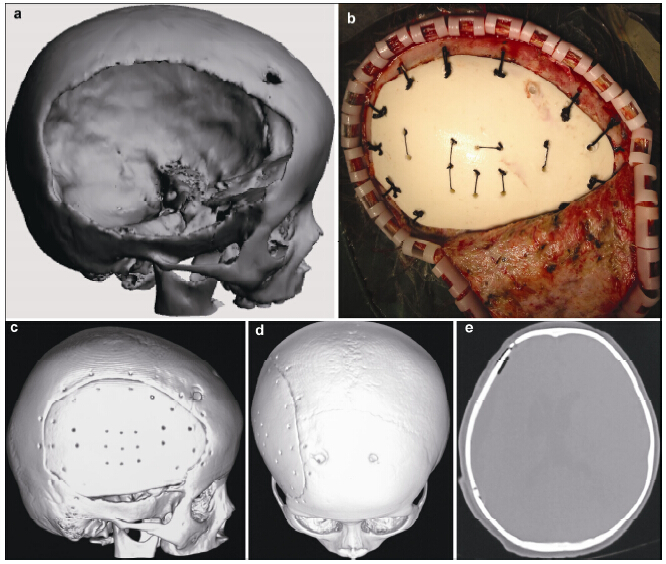

摘要 Objective: To evaluate the clinical results of repairing skull defects with biomimetic bone (nano-hap/collagen composites, NHACs) in children. Methods: Thirteen children with skull defects were treated with NHACs in our hospital. The NHACs molded with the help of a 3D printer were used in the operations. Results: All 13 operations were successful, and patients recovered without infection. Only one patient suffered from subcutaneous hydrops post-operation. The implanted NHACs remained fixed well after 1 year, and their CT HU values raised gradually. Skull shapes of children developed normally. Recovery of neurological and cognitive function was significant. Conclusions: NHAC, chosen to repair skull defects in children, can coexist with normal skull and reduce the negative effects on growth and development. NHAC could be a good choice for children with skull defects.

Abstract: Objective: To evaluate the clinical results of repairing skull defects with biomimetic bone (nano-hap/collagen composites, NHACs) in children. Methods: Thirteen children with skull defects were treated with NHACs in our hospital. The NHACs molded with the help of a 3D printer were used in the operations. Results: All 13 operations were successful, and patients recovered without infection. Only one patient suffered from subcutaneous hydrops post-operation. The implanted NHACs remained fixed well after 1 year, and their CT HU values raised gradually. Skull shapes of children developed normally. Recovery of neurological and cognitive function was significant. Conclusions: NHAC, chosen to repair skull defects in children, can coexist with normal skull and reduce the negative effects on growth and development. NHAC could be a good choice for children with skull defects.